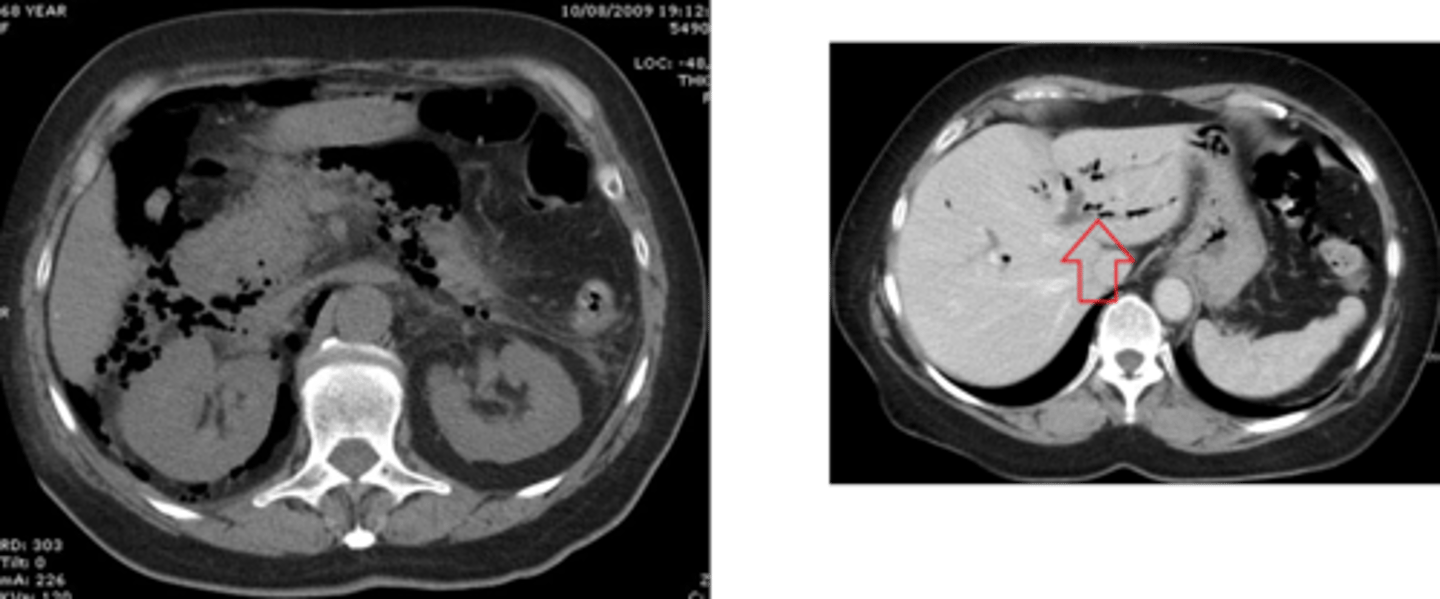

abdominal CT

contrast used with bowel perforations

gastrografin